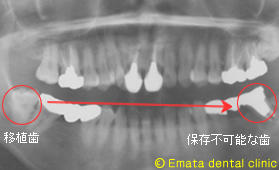

1本の歯を失った場合は、通常はブリッジになることが多いですが、隣の歯を削る大きな欠点があります。その他の治療としてインプラント治療がありますが、歯牙移植 という治療も選択枝にはあるわけです。

移植治療は、適応症が限られるためケースとしてはそれほど多いとは言えませんが、いろいろな面でインプラント同等、場合によってはそれ以上の効果があると考えています。

患者様は左下のブリッジの土台が腫脹して来院されました。大きな根の病気・歯根歯折も疑われます。抜歯の適応です。左下は2歯がなくなり、患者様の希望と適応症から、2歯欠損に移植とインプラントを両方行う治療計画にしました。

親知らずを移植歯に使用しました。大きさ、根の形態、歯根膜の状態、すべてに適応症の歯です。 |